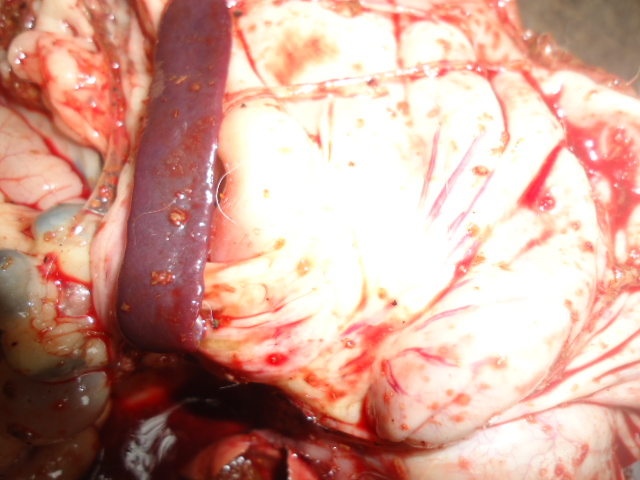

On aurait pensé en premier lieu à une intoxication alimentaire. On observe un météorisme, un liquide jaunâtre s’écoule de l’urètre lorsqu’on presse l’abdomen. A l’autopsie, on constate une accumulation de gaz dans les caeca (expliquant le météorisme), le foie est décoloré, friable et présente un aspect cuit. Les canaux hépatiques sont fortement irrigués, on constate une hypertrophie de la vésicule biliaire. On note une érosion de la membrane interne de l’estomac et la membrane externe est fortement irriguée. La rate est

hypertrophiée, les reins présentent des effusions sanguines.

En dehors de ces lésions à tropisme digestif, nous avons enregistré d’autres lésions hémorragiques. Au niveau des jeunes lapins morts, on observe un épistaxis moins prononcé, la trachée artère est hémorragique et sa membrane interne présente des grumeaux de sang. Les poumons présentent des effusions sanguines. Le cœur est flasque et à l’incision une quantité importante de sang noirâtre s’échappe.